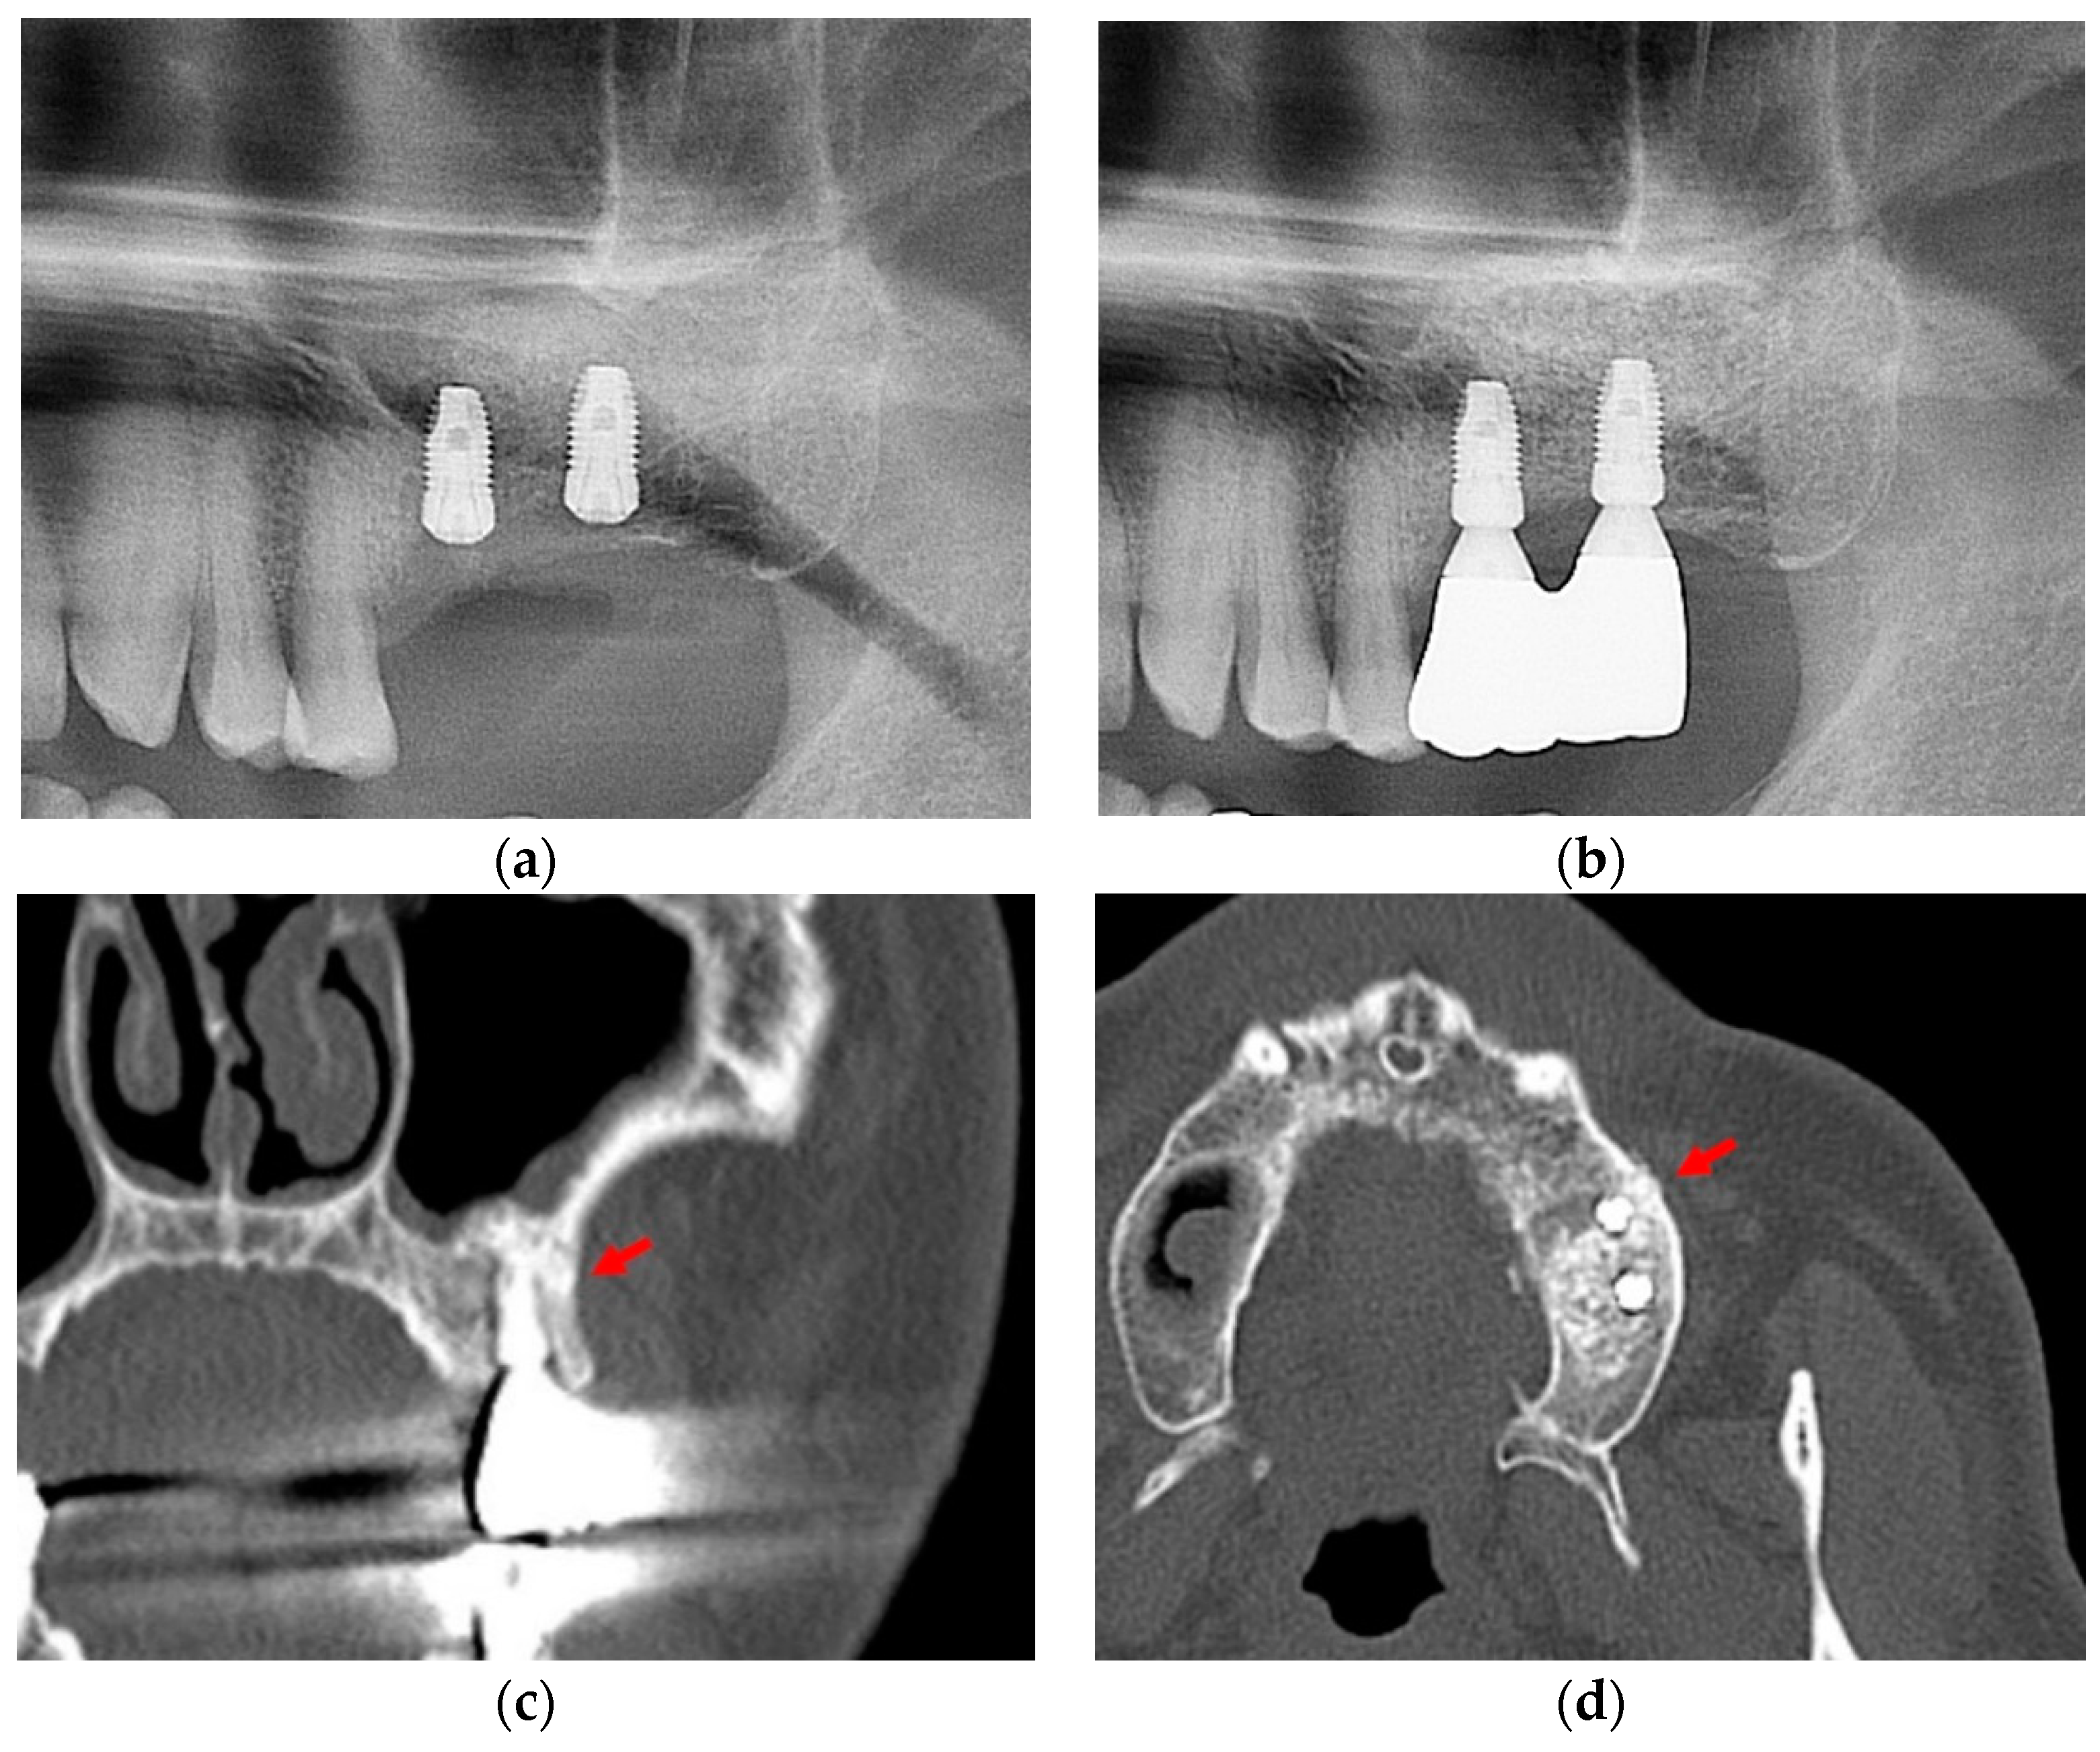

Minimally Invasive Lateral Approach through Circular Window with a Diameter of 5 to 6 mm for Maxillary Sinus Floor Elevation with Simultaneous Implant Placement: Retrospective Study

3. Results